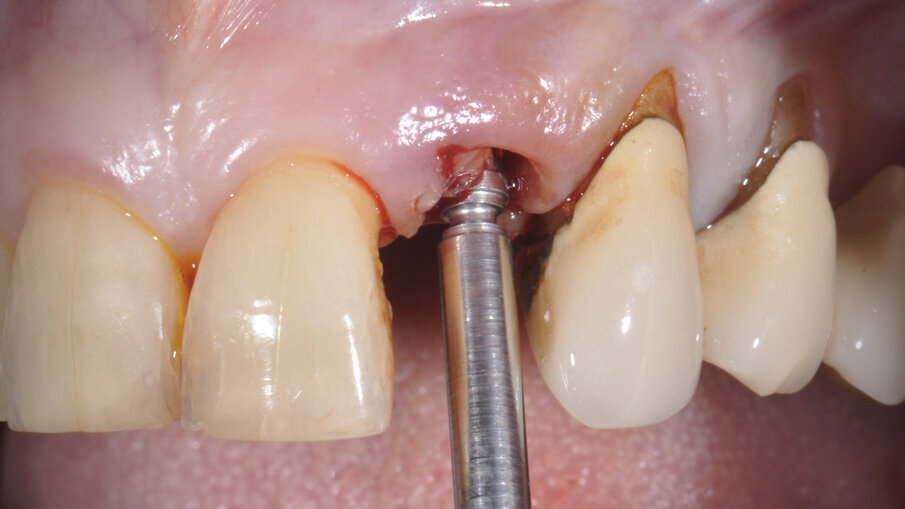

Il poter disporre di una tipologia di fixture estremamente orientata al conseguimento di elevati valori di stabilità primaria ha costituito un ulteriore elemento a favore di questa scelta. La paziente è stata sottoposta ad un trattamento preliminare a cielo coperto mediante levigatura radicolare. Il giorno dell’intervento, sotto profilassi antibiotica, è stata eseguita l’estrazione in maniera micro-traumatica e la rimozione mediante curettage dei tessuti infiammatori presenti. Non è stato eseguito un lembo di accesso, ma è stata verificata la presenza di tessuto osseo in sede vestibolare (Fig. 3).

Fig. 3_Alveolo post-estrattivo.